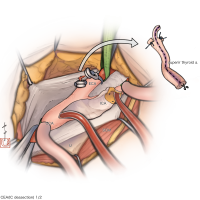

術後イラストシリーズ